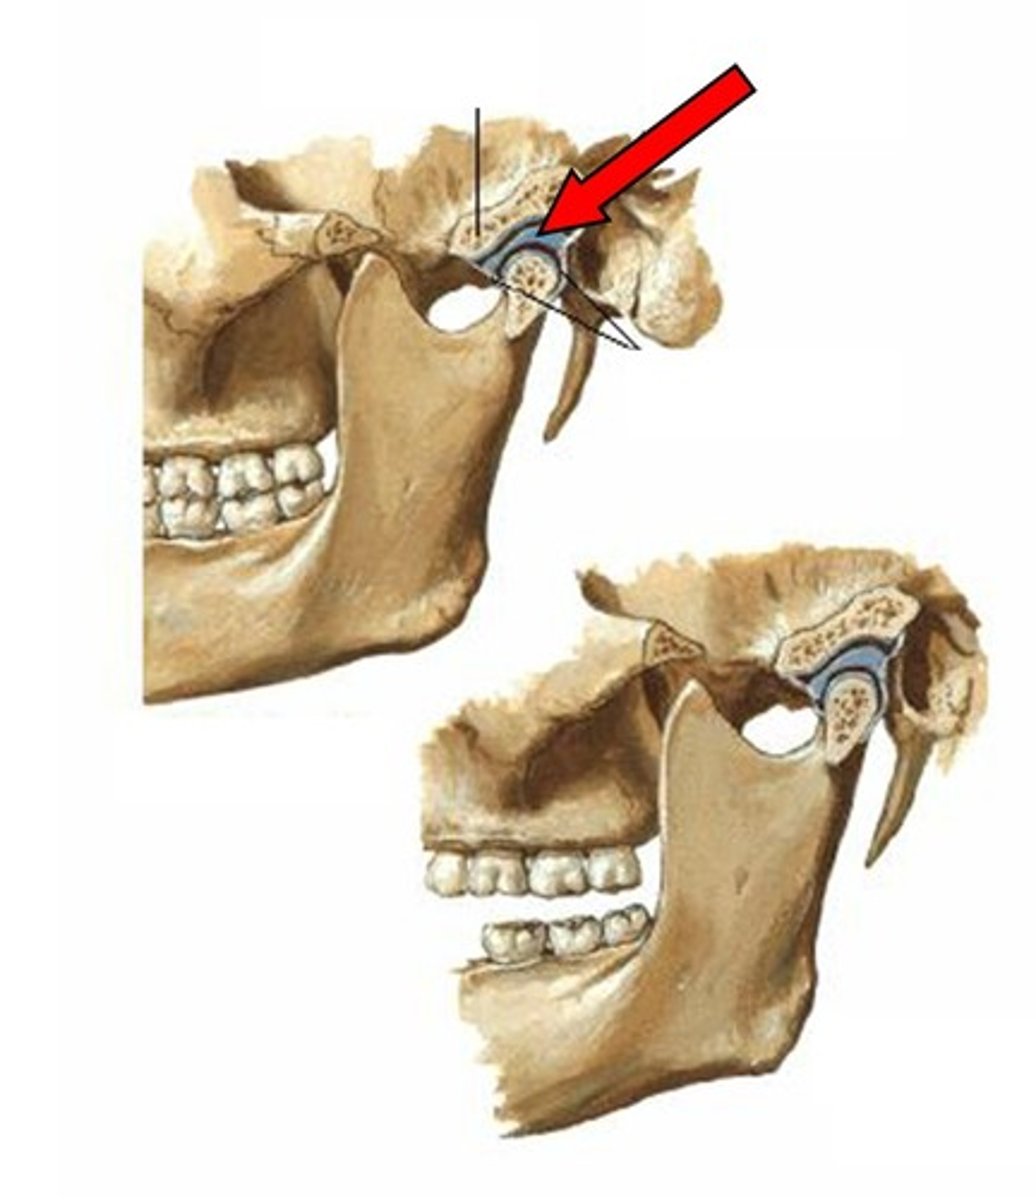

Articular capsule (temporomandibular joint)

Synovial membrane (temporomandibular joint)

articular disc (temporomandibular joint)